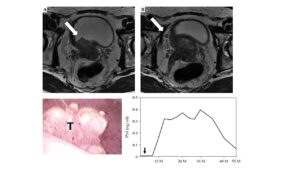

さらに58%の症例が高リスク因子を2つ、もしくは3つ有する症例でした。つまりこれらは私が治療手がけた高リスク症例のうちのトリモダリティ治療を行わざるを得なかった症例のデータであり、ホルモン療法を使わず小線源と外部照射の併用、もしくは小線源単独で完治している高リスク症例は含まれていませんので、すべての高リスク症例を集計して計算するとさらに非再発率は高くなるものと予想されます。従って他施設の高リスク前立腺癌に関する治療成績と比較される場合は、各施設のデータにおいてどの程度の重症高リスク前立腺癌を調査対象症例に組み入れているかという症例背景の差異を考慮する必要があります。私は、他施設において小線源治療やトリモダリティ治療の適応外と判断された難治性前立腺癌症例の多くを完治に導いてまいりました(もちろんこれら困難な症例の中には診断・治療時には画像上わからなかった潜在的骨転移を有する症例が一定の確率で存在し、こういったケースでは治療後再発という経過を辿ってしまうことは止むを得ません:上述の高リスク論文で再発した6症例は全例このような潜在的骨転移の存在が原因でした)。 上述の2017年に国際誌に公表した高リスク症例のお一人でPSA>20ng/ml, T3a, グリソンスコア4+5であった方のインタビュー(下段)がありますので参考になさってください。この方は小生のトリモダリティ治療後10年以上経過していますが、再発や、血尿・血便といった副作用もなく、元気に奥様とお暮しになっておられます。このほか、膀胱に浸潤した前立腺癌はT4と分類され明確に完治した症例の報告は調べ得た限りではないのが現状ですが、全骨盤への外部照射を併用したトリモダリティ治療により精嚢浸潤(+)、膀胱浸潤(+)、骨盤内リンパ節転移(+)つまりT4N1症例の完治症例も国際誌に公表しています(Journal of Cotemporary Brachytherapy, 2021)。Prostate cancer with nodular bladder invasion (stage T4N1) cured by low-dose-rate brachytherapy with seminal vesicle implantation in combination with external beam radiotherapy of biologically effective dose ≥ 220 Gy: a case report – PMC

Axial T2-weighted magnetic resonance images of the prostate. A) A large prostate tumor with hypo-intensity extended into the right bladder wall. The white arrow indicates the invasion of prostate cancer into the bladder. B) Bilateral seminal vesicles invasion. A lymphadenopathy is also observed in the right obturator lesion suggesting pelvic node lymph node metastasis (white arrow). Cystoscopy findings of the nodular bladder invasion of prostate tumor. A) An irregular surface of solid and nodular tumor is located in the right trigone, near the bladder neck. T – nodular bladder invasion of the prostate tumor. Prostate specific antigen (PSA) change after the treatment.Y axis shows PSA values. X axis indicates the period(months) after EBRT completion. The black arrow shows cessation of ADT. PSA indicates temporal increase after cessation of ADT, but continuous decrease was observed thereafter. PSA at the latest follow-up (six years after the completion of EBRT) is 0.01 ng/ml: Testosterone level recovered to the normal range value at 9 months after cessation of ADT